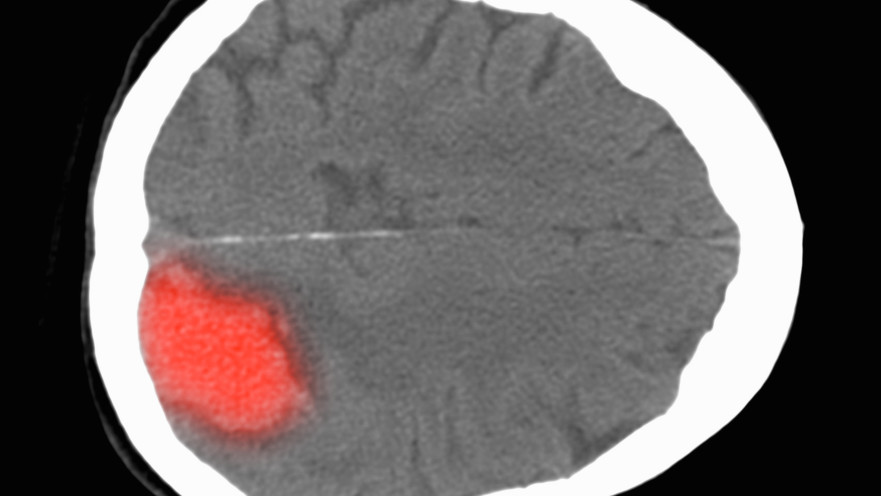

דימום מוחי, אילוסטרציה

דימום מוחי, אילוסטרציה | צילום: אינג'אימג'